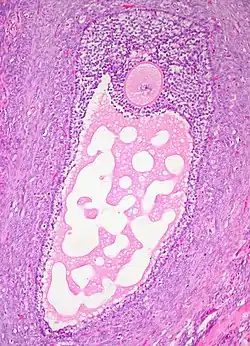

![]() Histology section of a mature ovarian follicle. The oocyte is the large, round, pink-staining cell at top center of the image.  | |

Ovarian follicles are the basic units of female reproductive biology. Each of them contains a single oocyte (immature ovum or egg cell). These structures are periodically initiated to grow and develop, culminating in ovulation of usually a single competent oocyte in humans.[5] They also consist of granulosa cells and theca of follicle.